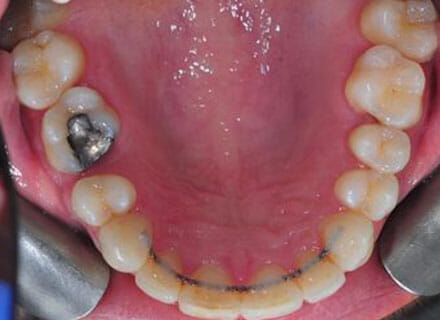

In this case the whole smile was affected by a tooth that was missing (a visible gap or hole at the side when smiling) and a tooth at the front that had grown the wrong side of the bite. We were able to correct the gap at the back by pulling the tooth behind forwards into the gap left by the previous extracted tooth. The clear brace also pushed the tooth at the front back in to the right position and the smile was massively improve. This case took around 18 months to complete.